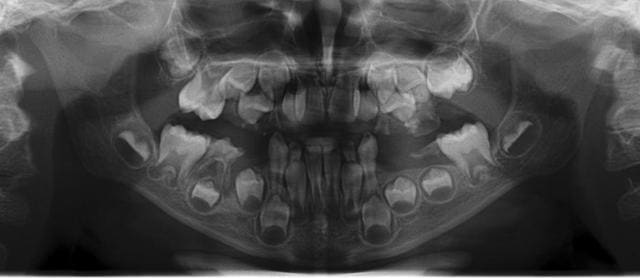

Mon champion du mois, 6 ans, 1ère visite chez le dentiste : l'avantage est que le plan de traitement est rapide à établir.

Quelques photos pour illustrer le sujet initial. Dommage que ces dents n'aient jamais eu de sealants.

Pour l'effraction pulpaire sur dent asymptomatique, je fais le protocole que Choixpeau avait mis sur le forum : hypochlorite puis adhésif directement au contact. Aucun problème à court terme pour le moment.

Si effraction plus importante : MTA.